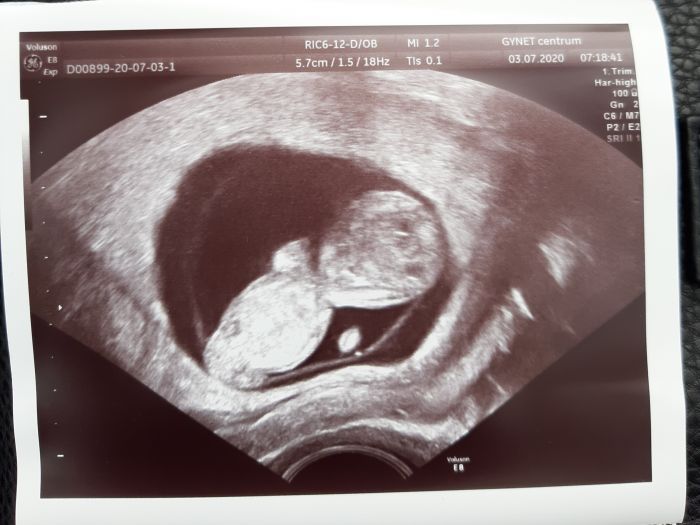

Autor: Luci 3.7.2020 v 06:23

Ahoj holky, my jsme dnes 11+3 a zatím vše v pořádku. Na screening jdu za týden a něco - v úterý. Jsem zvědavá, co nosím Pod srdcem :)

Luci to je krásný jak tam jsou dvě :) a co by jste chtěli? od každého jedno?

Ahoj holky, to jsou krásné fotecky. Luci, ty dvojky jsou kouzelné - jsou naprosto boží!